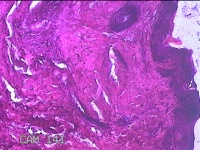

臀部肿物

性别

女

年龄

32岁

临床诊断

脂溢性角化病;皮肤感染

一般病史

颈部臀部丘疹数年。

标本名称

大体所见

灰白粉红色带皮肤样肿物1.8x0.5x0.2cm一个,表面糜烂。

图1